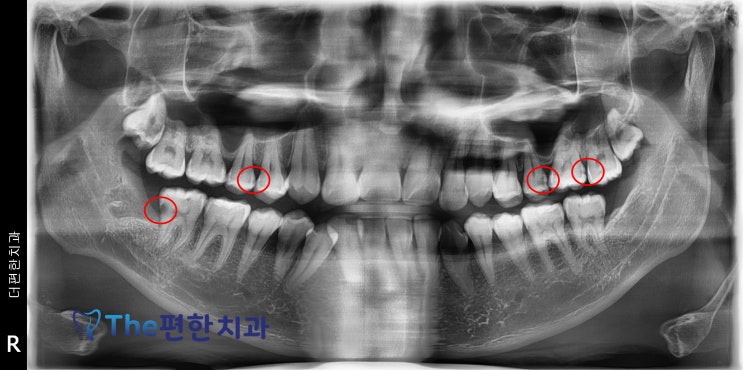

수완지구, 장덕동 더편한치과 충치치료 더 꼼꼼하게 합니다.